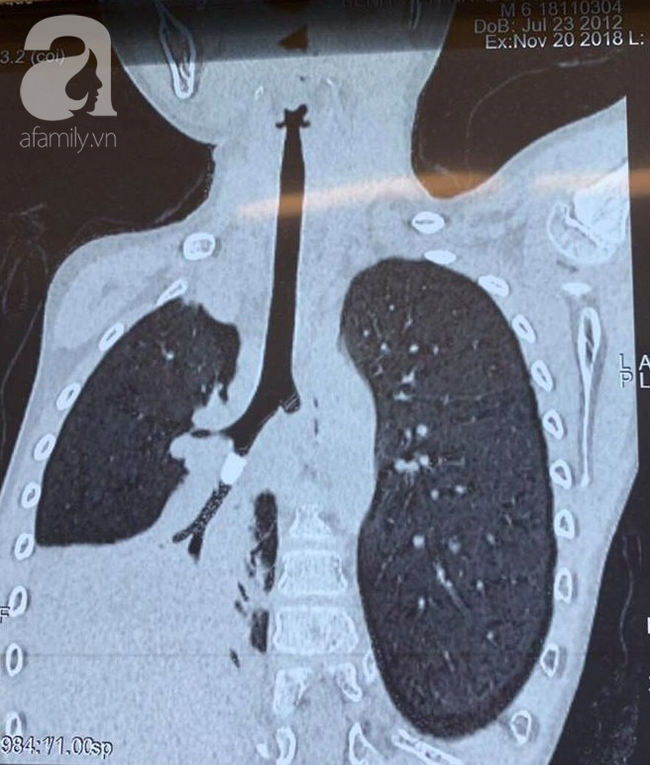

TS.BS Trịnh Hồng Nhiên, Trưởng khoa Hô Hấp BV cho biết sau khi hội chẩn, ông đã chú ý đến vùng bẫy không khí trong phim chụp X-quang phổi. Kết hợp với phim CT scan ngực cho thấy có sự hiện diện của một vật thể lạ trong phế quản, dạng hình trụ, bít lòng hoàn toàn nhánh phế quản S9.

Phổi bệnh nhi bị xẹp vì dị vật.

Điều này dẫn tới việc không khí không thể đi qua hoàn toàn vật thể, gây tắc và xẹp toàn bộ nửa phổi phải.